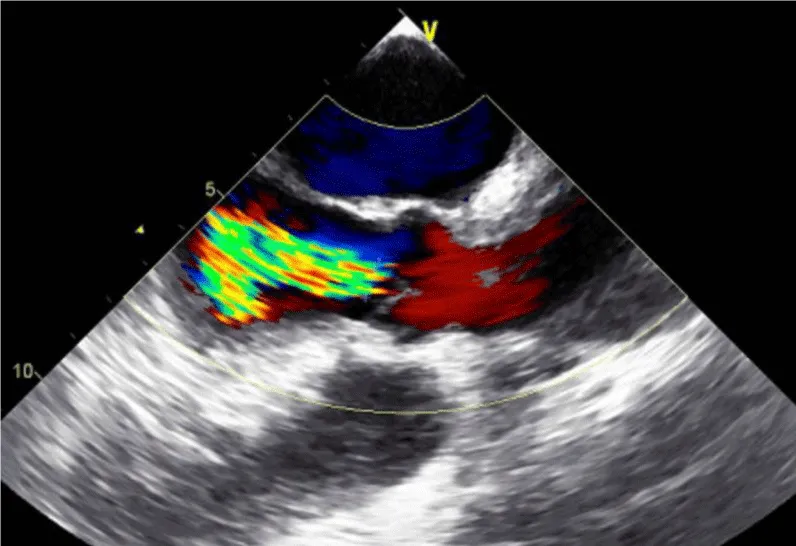

Her initial vital signs upon presentation to the hospital were; blood pressure: 161/76 mm Hg, heart rate: 96 beats per minute, respiratory rate: 27 breaths per minute. Physical exam revealed a cardiac auscultation findings of a grade 2 diastolic murmur which was loudest at the 2nd right intercostal space as well as a grade 2 systolic flow murmur. Cardiac biomarkers were elevated with initial troponin-I of 0.33 ng/mL, peak of 2.28 ng/mL and subsequent down trend. Electrocardiography (Figure 1) showed sinus rhythm with anterior and inferolateral T wave inversion and chest radiograph (Figure 2) was unremarkable. She underwent coronary angiography which revealed normal coronary arteries. The takeoff of the right coronary artery (RCA) was noted to be superior and anterior to its normal position (Figures 3A and 3B). Transthoracic and transesophageal echocardiography (TEE) revealed normal left ventricular systolic function and severe insufficiency of the aortic valve with Quadricuspid morphology (Figure 4A in Diastole, Figure 4B in Systole, Figure 4C Long Axis of the aortic valve). She underwent aortic valve replacement with a # 19mm ON-X mechanical valve. Intraoperatively it was noted that the ostium of the right coronary artery was over the aberrant leaflet. Her postoperative course was complicated by the development of supraventricular tachycardia, posteriorly localized pericardial effusion, severe hemolytic anemia, renal failure and pancreatitis leading to her death eleven days after the surgery.

Figure 4c: Long Axis of the aortic valve demonstrating severe aortic Insufficiency.